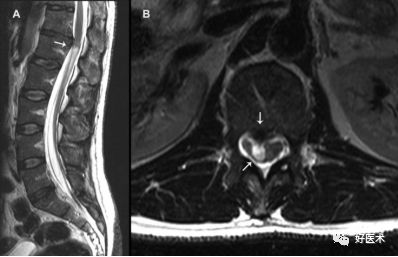

我们先来看一个病例:

诊断